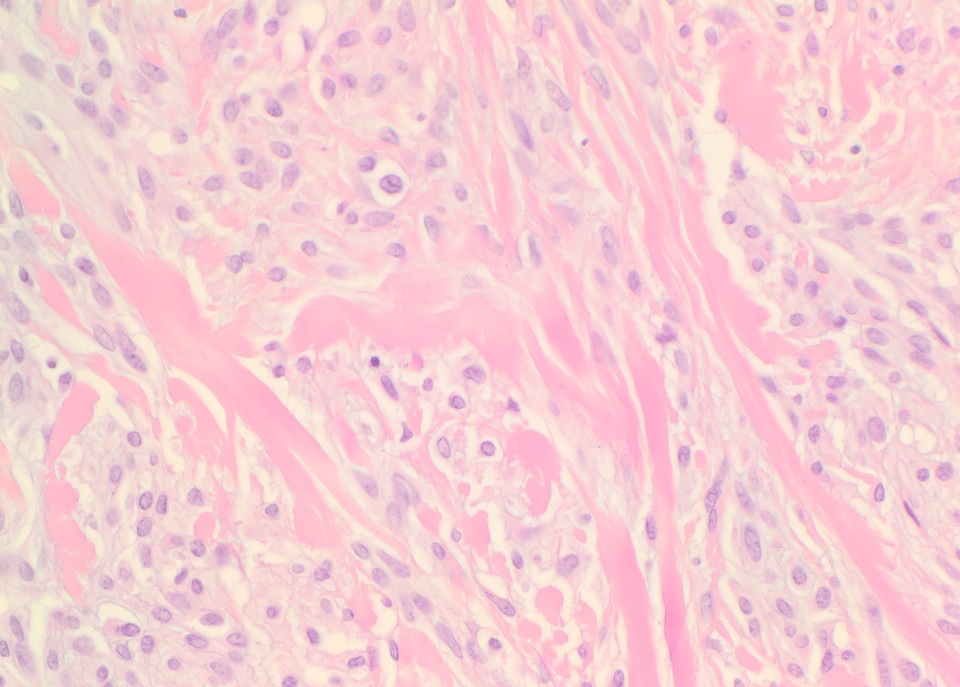

Micro images:

The conventional histologic appearance is of bland fibroblast-like spindle cells with relatively short, stubby nuclei. The cells are interspersed between collagen bundles and a variable amount of adipose tissue. The stroma can show hyalinization and / or myxoid change. Mast cells may be conspicuous (Goldblum: Enzinger and Weiss's Soft Tissue Tumors, 6th ed, 2013, Am J Surg Pathol 2016;40:361). Several different variants of MTMF have been described: cellular, infiltrating, collagenized / fibrous, lipomatous, myxoid, epithelioid and deciduoid-like. Areas of smooth muscle, bone and cartilage can be seen (Am J Surg Pathol 2009;33:1085). Rare tumors may show a neurilemmoma-like pattern. "Symplastic" or degenerative cytologic atypia - enlarged, hyperchromatic, multinucleated cells - can be present (Am J Surg Pathol 2016;40:361).

Micro images:

The conventional histologic appearance is of bland fibroblast-like spindle cells with relatively short, stubby nuclei. The cells are interspersed between collagen bundles and a variable amount of adipose tissue. The stroma can show hyalinization and / or myxoid change. Mast cells may be conspicuous (Goldblum: Enzinger and Weiss's Soft Tissue Tumors, 6th ed, 2013, Am J Surg Pathol 2016;40:361). Several different variants of MTMF have been described: cellular, infiltrating, collagenized / fibrous, lipomatous, myxoid, epithelioid and deciduoid-like. Areas of smooth muscle, bone and cartilage can be seen (Am J Surg Pathol 2009;33:1085). Rare tumors may show a neurilemmoma-like pattern. "Symplastic" or degenerative cytologic atypia - enlarged, hyperchromatic, multinucleated cells - can be present (Am J Surg Pathol 2016;40:361).